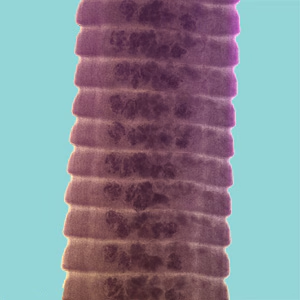

Hymenolepis proglottids.